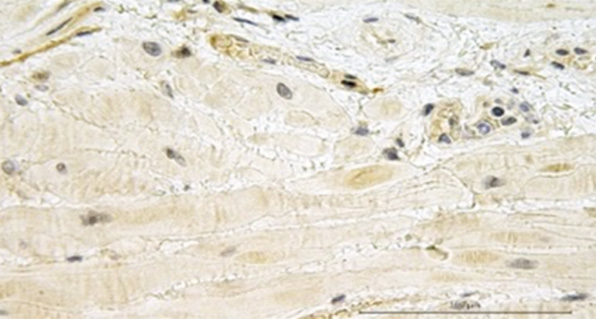

Микроскопическая картина биоптатов миометрия группы 3 существенно не отличалась от картины биоптатов группы 2 и представлена гипертрофированными миоцитами с тонкими прослойками соединительной ткани. В отличие от микроскопической картины основной группы, в образцах миометрия контрольной группы визуализированы участки децидуальной ткани с мелкоочаговой мононуклеарной инфильтрацией и неравномерным полнокровием сосудов (рис. 2, е, f).

Рис. 2. Микрофотографии биоптатов миометрия из маточно-плацентарной области: a — ворсина хориона в биоптате миометрия при плацентарной адгезивно-инвазивной патологии (PAS 3a–c); b — децидуальная оболочка в биоптате миометрия при плацентарной адгезивно-инвазивной патологии (PAS 3a–c); c — фрагмент миометрия группы сравнения с полнокровием капиллярного русла из области прикрепления плаценты; d — фрагмент миометрия группы сравнения с участком децидуальной ткани из области прикрепления плаценты; e, f — фрагмент миометрия контрольной группы с участком децидуальной ткани. Окраска гематоксилином и эозином, увеличение ×200